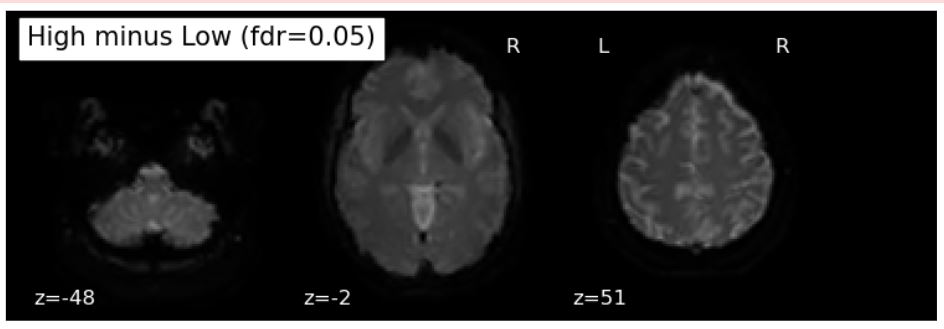

First, this project involved correcting the format of my dataset. I had to convert it to BIDS format and preprocess the Nifti files with fmriprep. These steps took longer than expected. So far, only one participant’s files have been converted to BIDS format and preprocessed. However, I was able to run a first-level general linear model on this participant to present: 1) BOLD activity in the visual cortex and the superior frontal gyrus (SFG) when images were shown at this participant (effect of interest) and 2) no significant region of BOLD activity when contrasting high vs low calorie snacks.

Figure 2. BOLD activity contrast between high vs low calorie snacks (for run #1 of one participant)